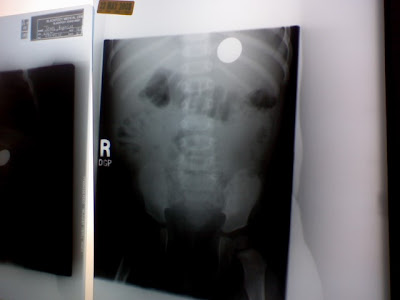

Finally Xray came and took one last picture to make sure the penny was still in her stomach after 6 days. None of us really had the faith that it would pass on it's own. After being in the stomach that long it was just too big.....Only aunt Abby had the faith and fasted for Kynlee that it would come out on it's own.

And it did! The Xray showed that in less than 12 hours it had passed thru her stomach and was making it's way to the exit. We were SO relieved. Honestly it couldn't have come out any better!